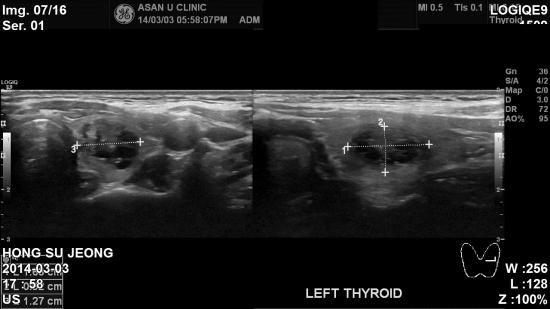

건강검진에서 실시한 갑상선 초음파상 이상소견으로

정밀진료위해 내원하신 41 여자분이십니다.

본원에서 초음파 검사상 우측에 1.42cm , 좌측에 1.67 cm 의 결절이 발견되어

각각 세포검사를 시행하였습니다.

검사결과 좌측결절(1.67 cm )이 갑상선 유두암으로 진단되었고

대학병원으로 전환하여 치료예정이십니다.